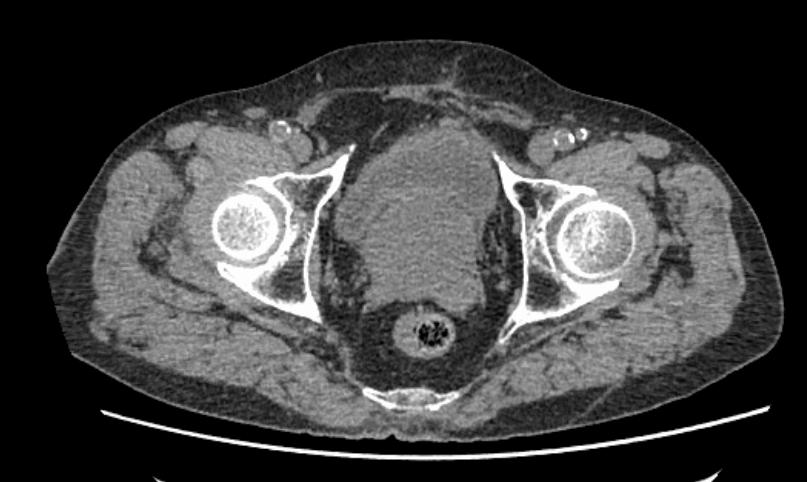

刘春晓教授接诊后,为陈大爷完善盆腔CT血管造影检查,发现他的前列腺体积已达到67×55×58毫米。据了解,正常年轻男性的前列腺大概就板栗大小,从40岁以后前列腺会逐渐增大。由于陈大爷已过百岁,他的前列腺也增大明显,已经达到了鹅蛋的大小,增生的前列腺挤压尿道,导致陈大爷排尿困难,膀胱内残余尿量增多,还有双肾积水等问题,需要尽快进行手术治疗。